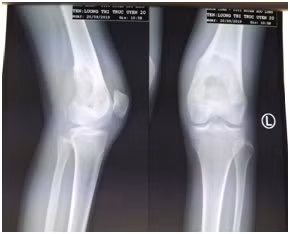

![]() |

| Phim chụp X-quang phần xương đùi của bệnh nhân |